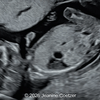

A 30-year-old G2P1, with an unremarkable history, presented to our office in the 21st week of her pregnancy for a routine second-trimester screening. Our examination revealed the following findings: